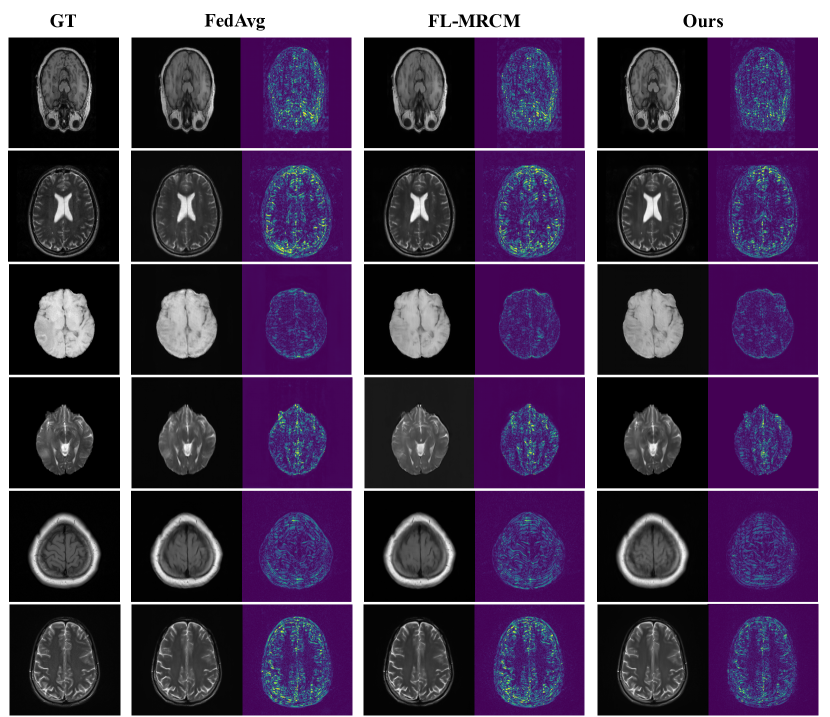

Refer to caption

Figure 7: Visualization of MRI image reconstruction with IXI, BraTS2020 and fastMRI as locally held data. We compare ours with two other FL methods: FedAvg and FL-MRCM. Each FL method trains with T1/T2- weighted IXI, BraTS2020, fastMRI as local data and tests on T1 IXI, T2 IXI, T1 BraTS2020, T2 BraTS2020, T1 fastMRI, T2 fastMRI test set respectively. The second column of each sub-figure is the error map (absolute difference) between the reconstructed images and the ground truth (GT).

For local training, we train each Tksubscript𝑇𝑘T_{k} with Adam optimizer and a constant learning rate of 0.0001 for 20 epochs following (Gong et al. 2022b). For the second stage of distillation, we update the networks with Adam optimizer and a constant learning rate of 0.0001 for 100 epochs. In Figure 7 we show qualitative results of the reconstructed images as well as the comparisons with two other FL methods (McMahan et al. 2017; Guo et al. 2021).